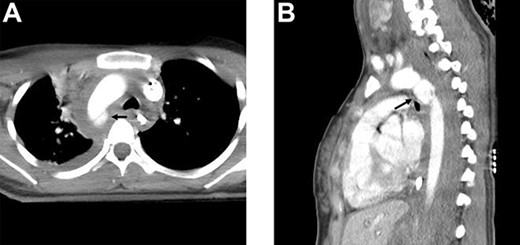

Contrast-enhanced computed tomography (CT) of the chest revealed SIT with dextrocardia and a saccular pseudoaneurysm at the aortic isthmus with a mediastinal hematoma (Figs 2a and b). Abdominal CT showed intraperitoneal fluid and free air, while CT of the head revealed multiple facial fractures. Radiographs of the limbs showed a right humeral fracture.

Contrast-enhanced CT scan showing a saccular pseudoaneurysm at the aortic isthmus (arrow) with a mediastinal hematoma; (a) transverse view and (b) lateral view.